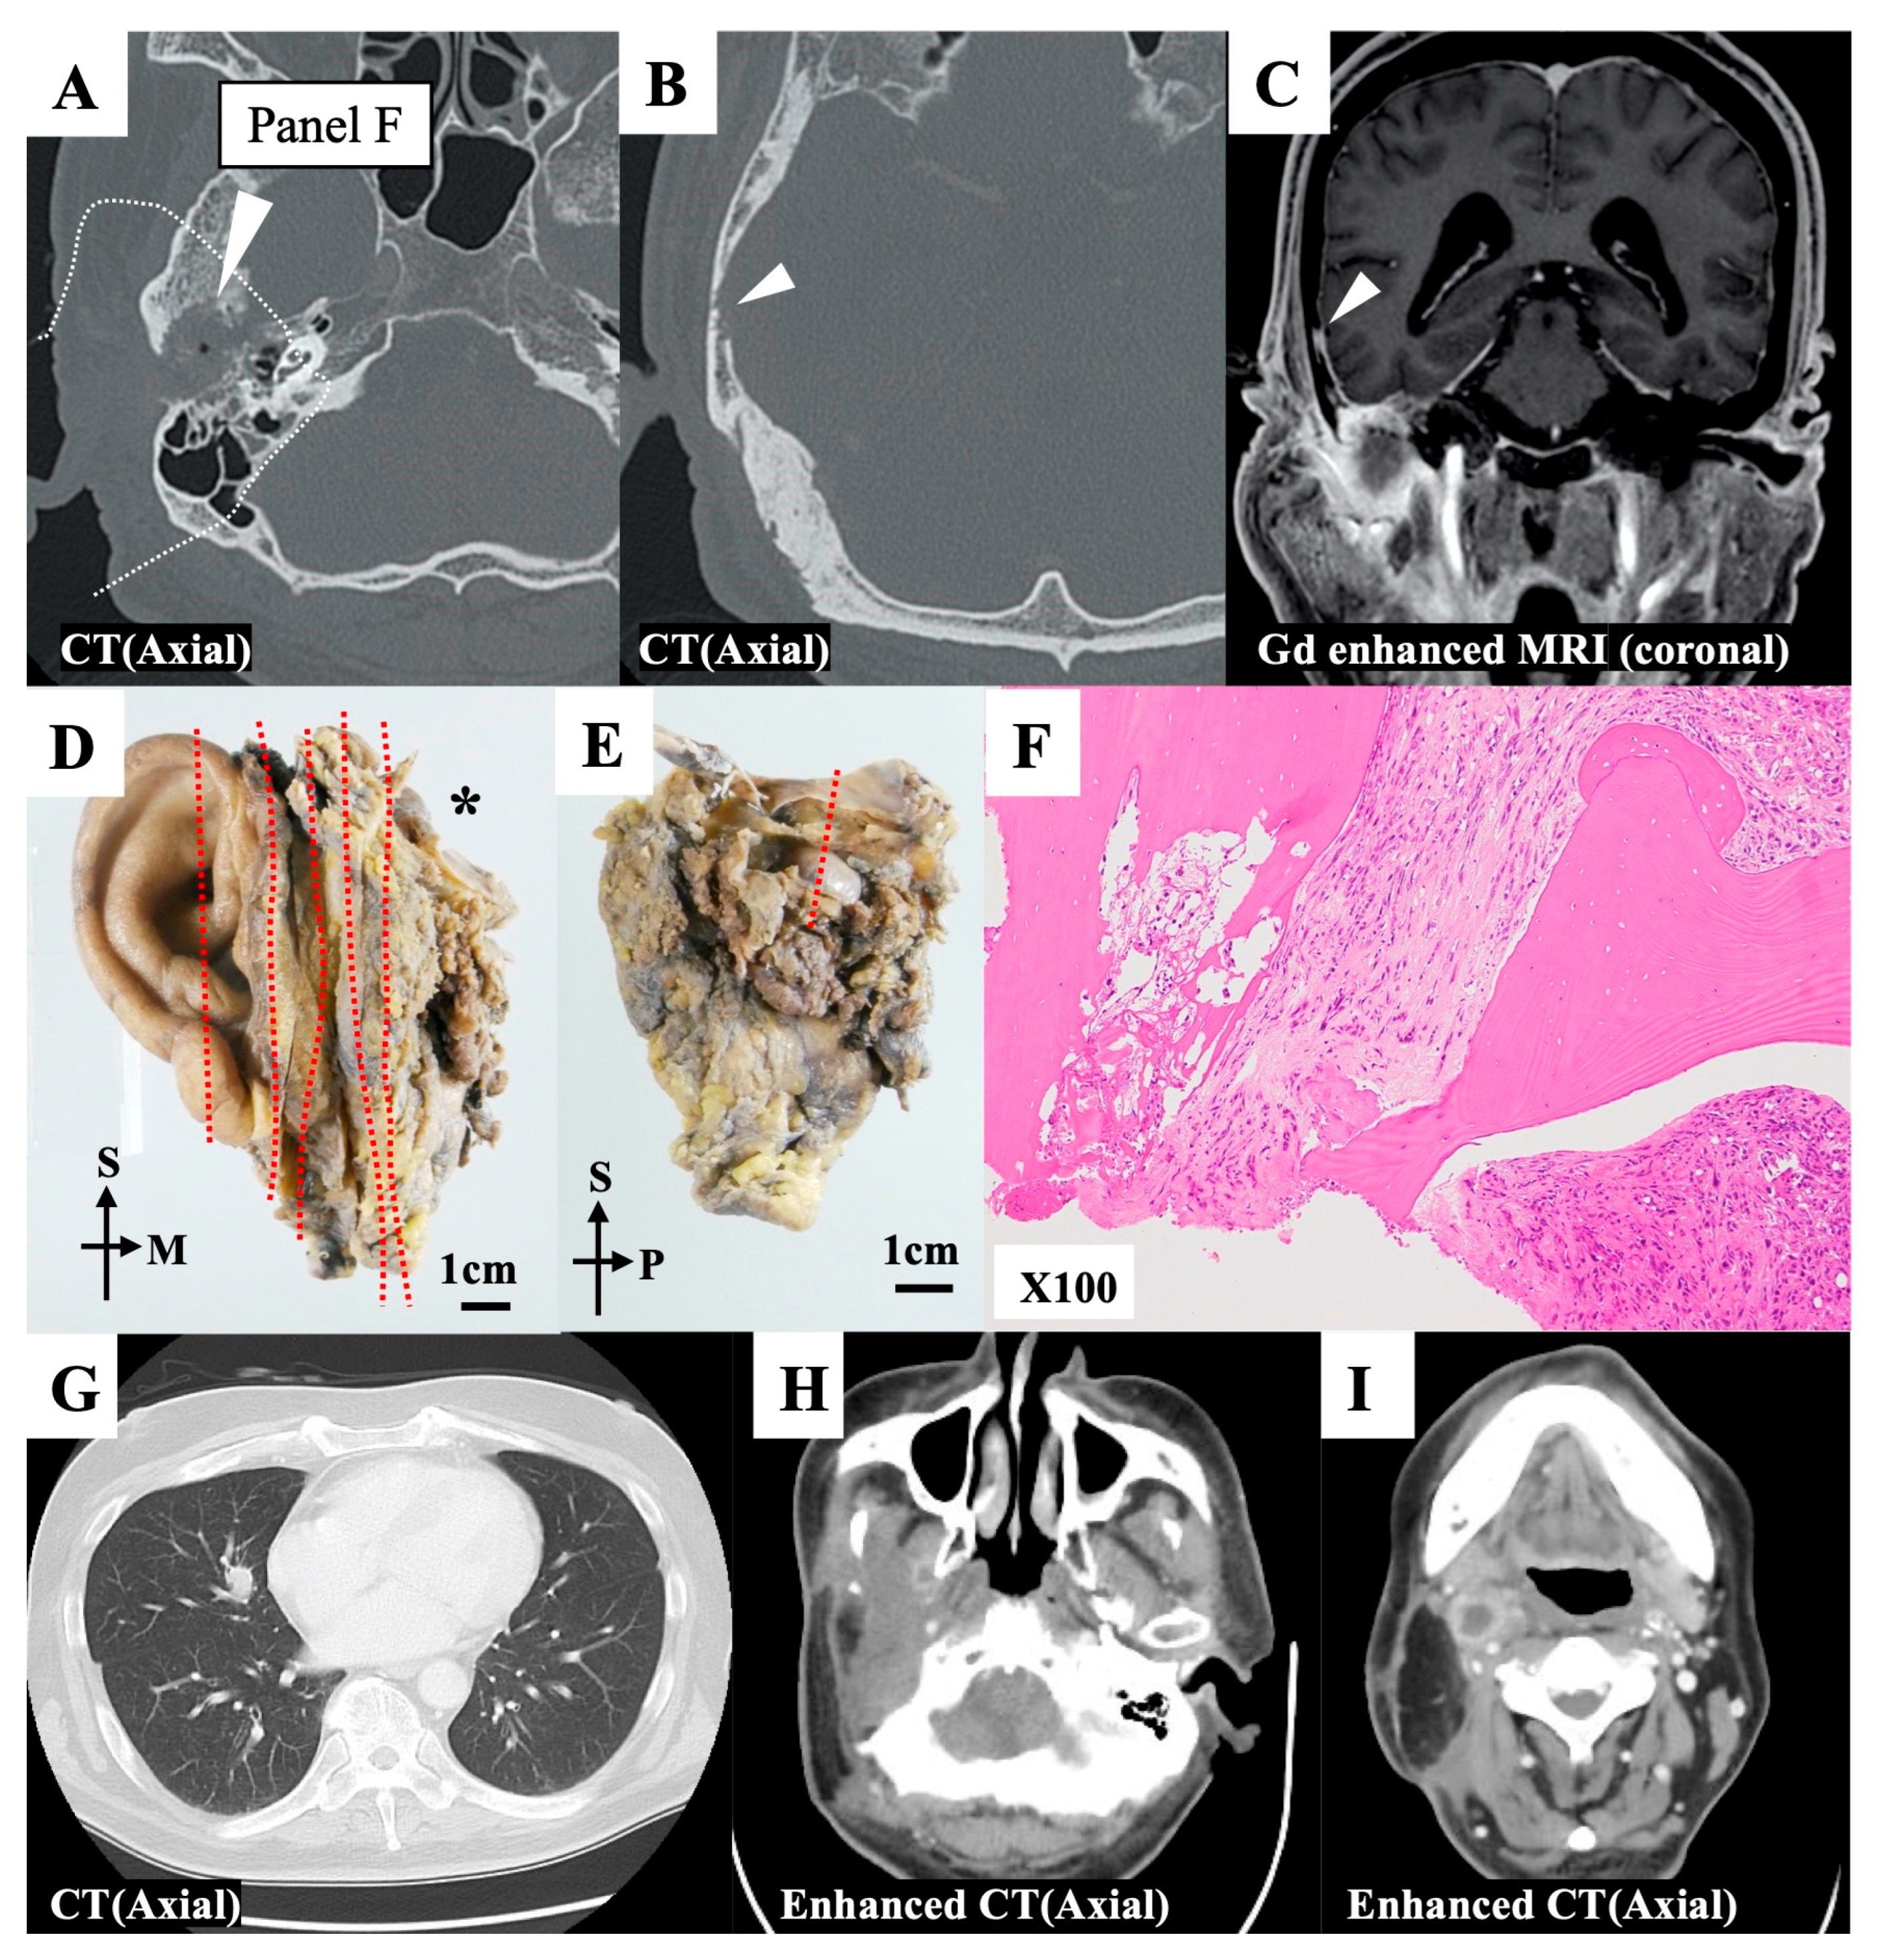

3.2.1. Case 20

| 20 | Surgery * | a–eLTBR | 3 | 0 | 3 | 0 | 0, 0, 0 | + | + | + | + | + | ★ | + | T | ||||||||||||